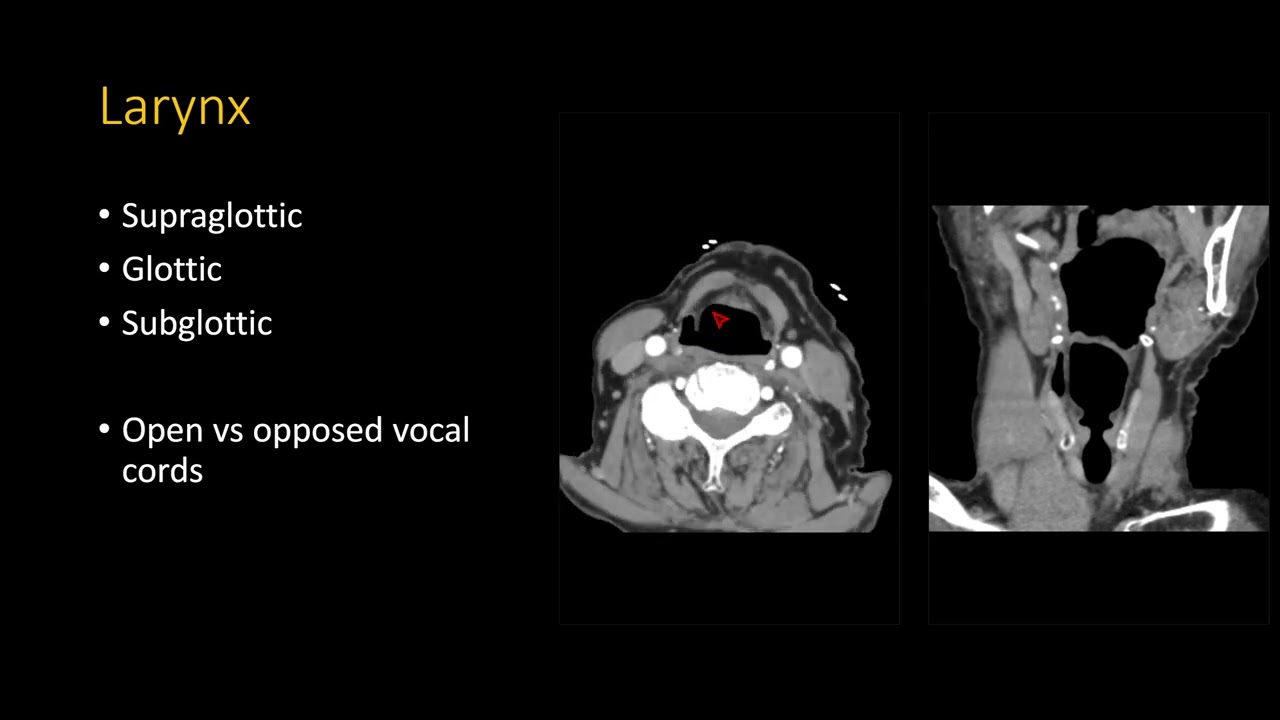

Neck CT search pattern

A search pattern for reading neck CTs. The original presentation, hosted at RadPPTX (link below) has fully scrollable images with an integrated PACS.